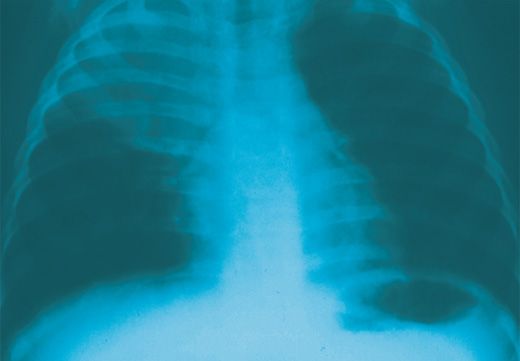

Images of allergic fungal rhinosinusitis, Wegener granulomatosis, interstitial lung disease, and other respiratory disorders show up in this photo essay.

Acute bronchiolitis, COPD, giant bullous emphysema, hypersensitivity pneumonitis, and pulmonary tuberculosis may present diagnostic challenges.